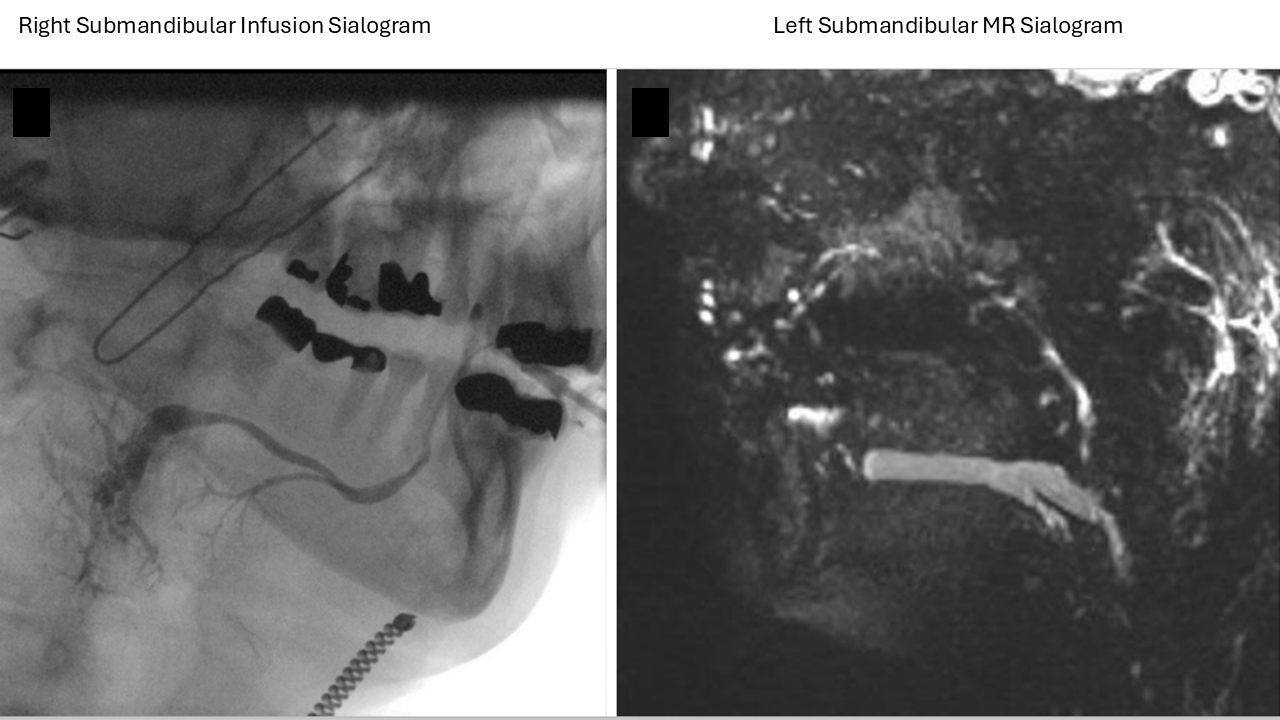

Discussion Points: Infusion sialography - diagnostic and therapeutic; MR sialography; Submandibular ductal stenosis; Anatomic variants

78 yo with

Right SMG pain and swelling with meals for 1 year

Left SMG h/o recurrent stones over 15 years –

- some spontaneous extrusions

- multiple removals in office with intraoral incisions

- currently with left smg discomfort with meals